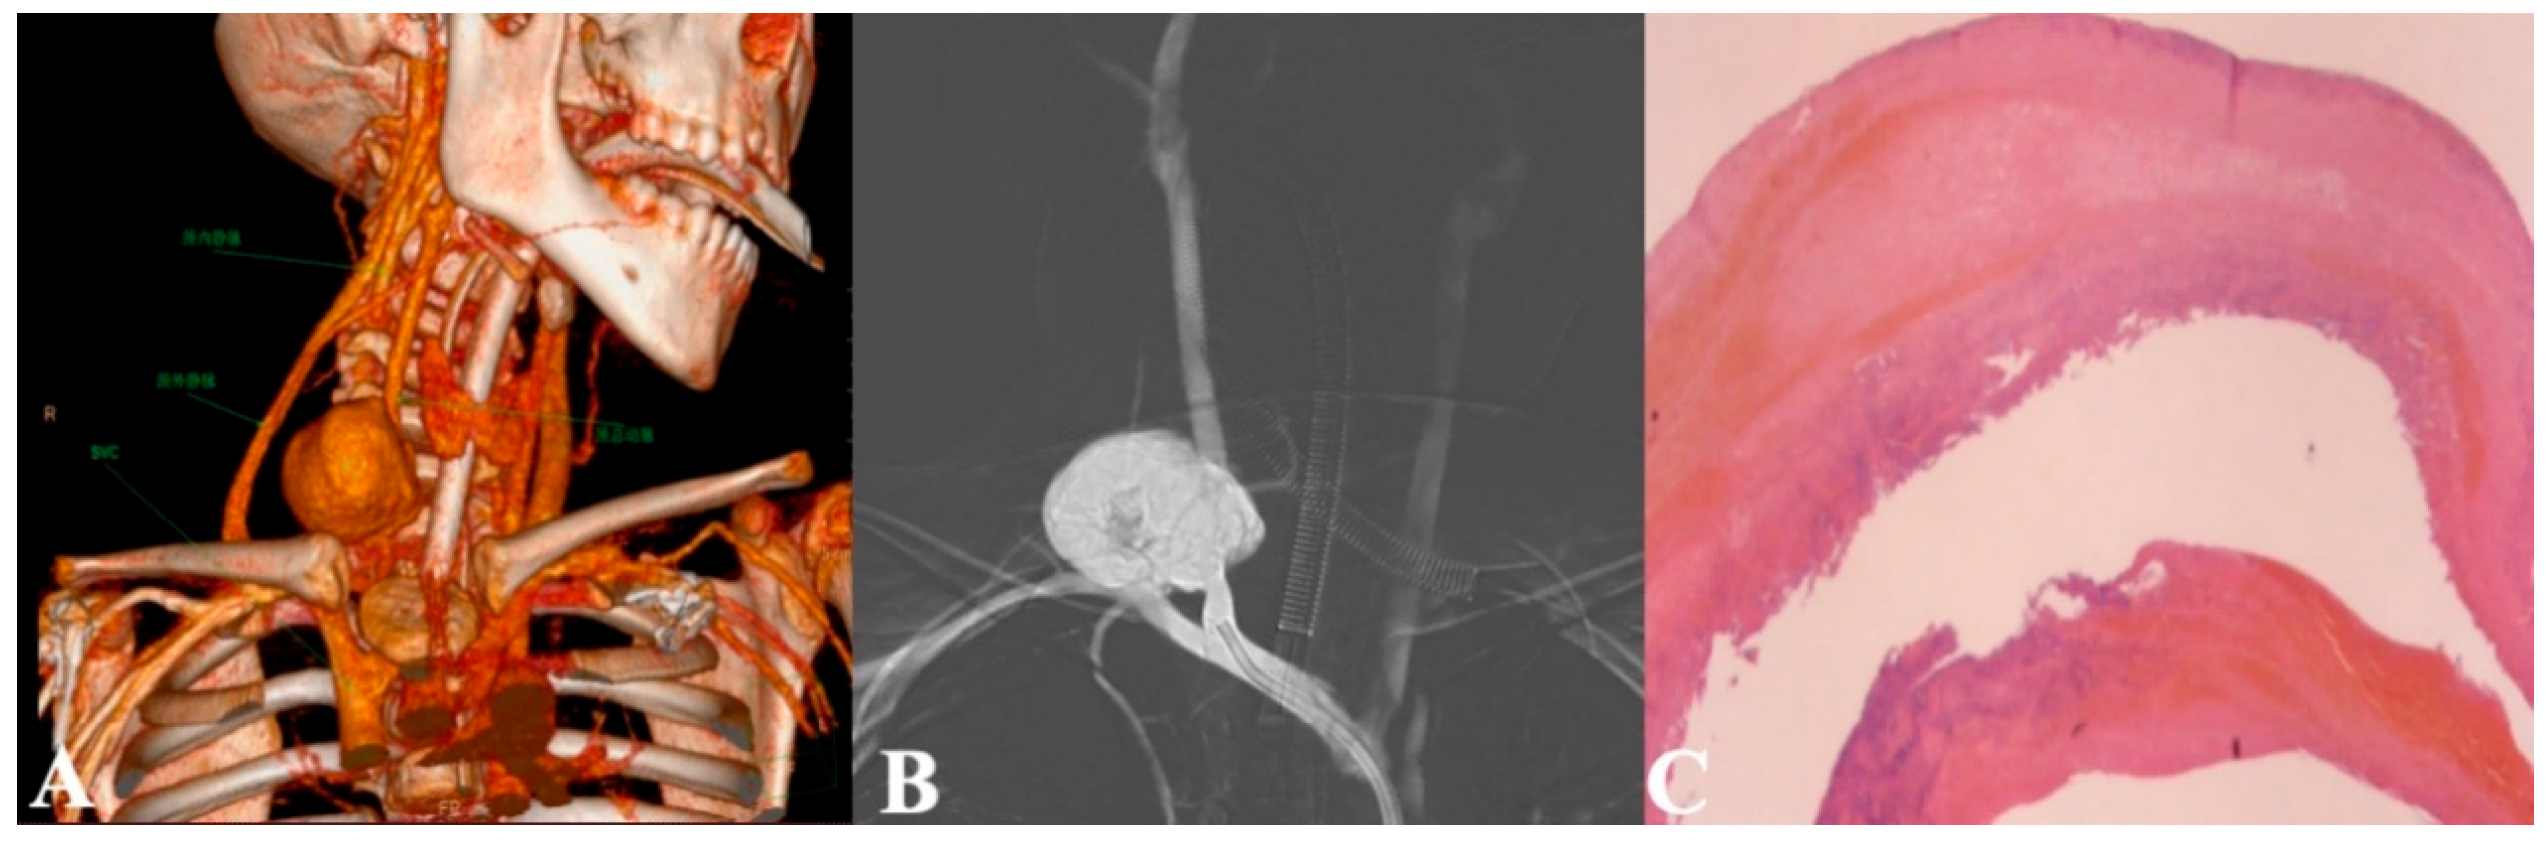

Figure 3: (A): Presurgical CT contrast scan suggesting a common carotid artery pseudoaneurysm: 3-D reconstruction coronal plane; (B): Arteriogram demonstrating a pseudoaneurysm of the right common carotid artery; (C): Pathologic examination of the carotid pseudoaneurysm, mainly composed of thrombus and fibrous components, accompanied by infiltration of inflammatory cells.

Emergency surgery was attempted to repair the artery. Initially, a guidewire was inserted via the right femoral artery, followed by right common carotid artery angiography, which revealed a large pseudoaneurysm of the right common carotid artery. The cerebral circle of Willis was found to be intact, and no abnormalities were observed. Subsequently, a 6 F balloon was deployed to completely occlude the aneurysm orifice, and angiographic findings indicated no blood flow through the aneurysm or the right common carotid artery. A 2.5 cm horizontal incision was then made along the original ECMO cannulation site in the neck, which revealed a fragile vessel wall with significant bleeding. The balloon was withdrawn after occluding the superior and inferior ends of the orifice, and the aneurysm wall was resected. Direct suturing and ligation were performed at the superior and inferior ends. Subsequently, the vessel is completely isolated and repaired. Digital subtraction angiography (DSA) assessment showed adequate collateral blood supply, allowing successful direct suturing and closure of the artery. Postoperative pathology confirmed the pseudoaneurysm diagnosis (Fig. 3C). The patient recovered well, with resolution of hoarseness and no neurological complications. Monthly ultrasound surveillance over an 8-month follow-up period revealed no detectable thrombi or adverse sequelae.